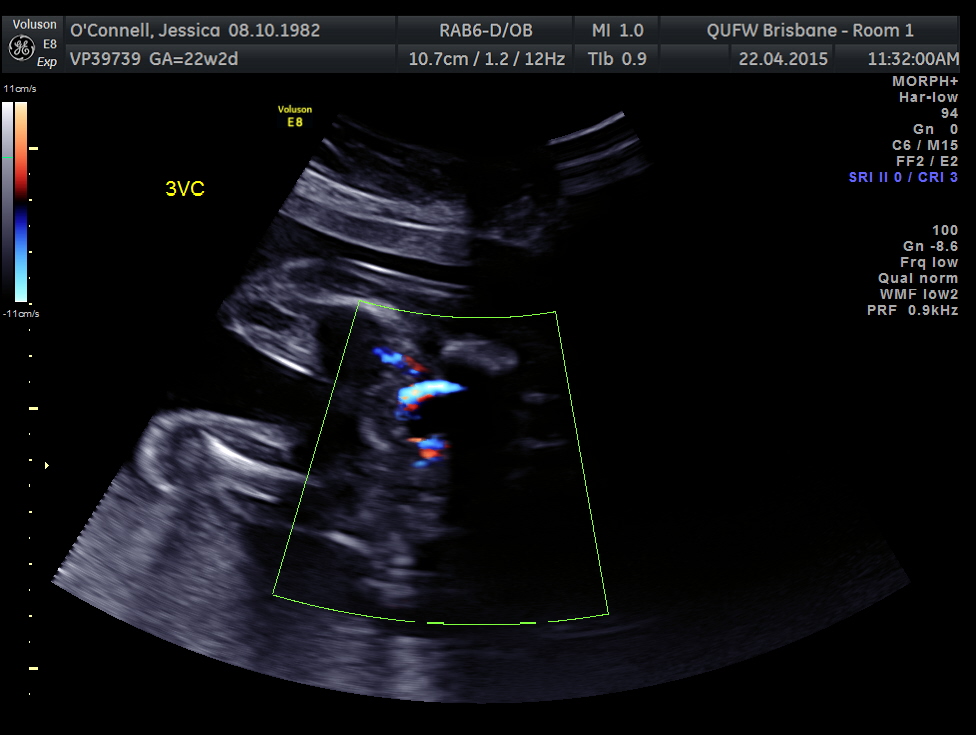

Just wondering what everyones guesses are boy or girl?Attachment 24886

do you have one without the color doppler? I dont see anything screaming boy but the color doppler in the way I cant be sure